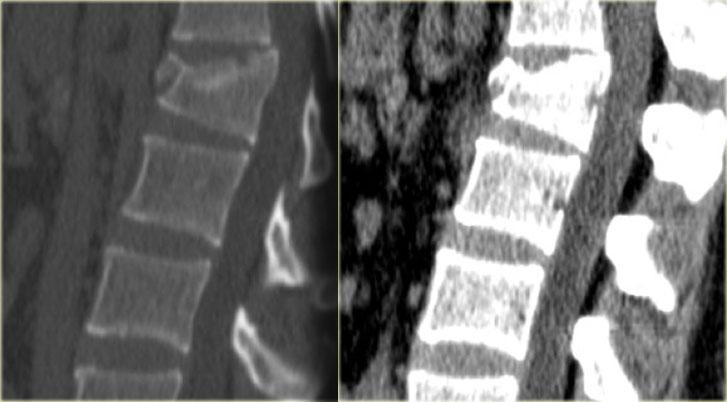

Hình ảnh bên trái của một nam giới 31 tuổi.

Anh ta đang làm việc trên mái nhà, ngã từ độ cao khoảng 5 mét và tiếp đất bằng hai chân.

Anh ta than phiền đau ở chi dưới bên trái và vùng thắt lưng.

Trước tiên hãy quan sát các hình ảnh, sau đó tiếp tục đọc.

Trên phim X-quang cho thấy tổn thương tăng gấp khúc của L1 với sự tổn thương cột trước và có thể tổn thương cột giữa.

Các tái tạo mặt phẳng đứng dọc trên CT cho thấy phần sau thân đốt sống có chiều cao bình thường, nhưng có một phần tổn thương ở phía sau thân đốt sống.

Hiện vẫn còn tranh luận về cách điều trị cho những bệnh nhân này và liệu MRI có vai trò gì trong những trường hợp này hay không.

Nếu đánh giá theo hướng tích cực, có thể gọi đây là tổn thương hai cột, đòi hỏi phải phẫu thuật cố định.

Nếu đánh giá theo hướng thận trọng, có thể gọi đây là tổn thương chỉ ảnh hưởng nhẹ đến cột giữa.

Bên trái là hình tái tạo theo mặt phẳng coronal và hình ảnh axial tại mức độ gãy xương.

Tiếp tục với MR.

Các hình ảnh MRI cho thấy phù tủy xương ở thân đốt sống bị tổn thương, nhưng không có tổn thương phần mềm bổ sung.

Dựa trên việc MRI không cho thấy bất kỳ phát hiện bổ sung nào, bệnh nhân này được điều trị như trường hợp tổn thương một cột.

Tham khảo ý kiến phẫu thuật chỉnh hình khuyến nghị điều trị bảo tồn với nẹp TLSO.

Ngày nay có xu hướng điều trị bảo tồn các chấn thương cột sống ngực-thắt lưng này, ngay cả khi có tổn thương nhẹ ở cột giữa.

Vai trò của MRI trong những trường hợp này vẫn chưa được xác định rõ ràng.